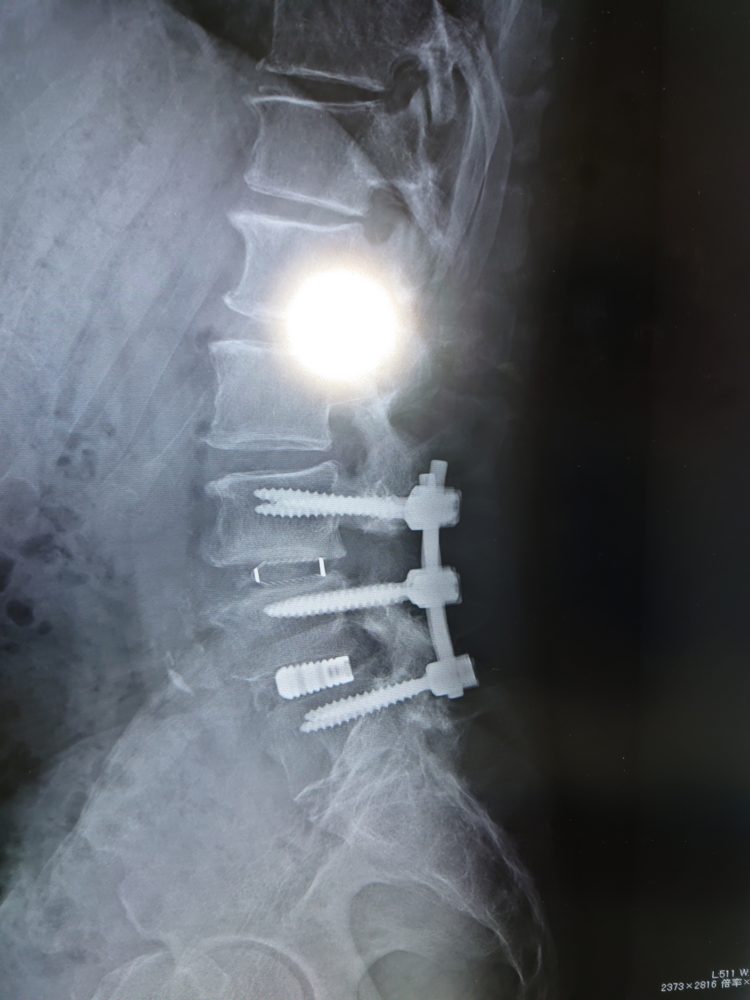

このボルト、、、前回のボルトを外して新機種導入、って。。。パチンコかよ(-_-;)・・・完全ロボコップにまた一歩前進、って。。。チタン合金かよ(T_T)/~~~左右で6本つなぎ合金も長さが二倍に(-。-)y-゜゜゜絶対転ばないように、と担当医から入念に注意m(_ _)m

骨の隙間?前回は白く見えるキャンバー。。。今回はちょっとおしゃれな半透明?解りますか?最新のキャンバーだそうです(担当医より)その上の骨も削っているんですよ?。。。わかるかな~?